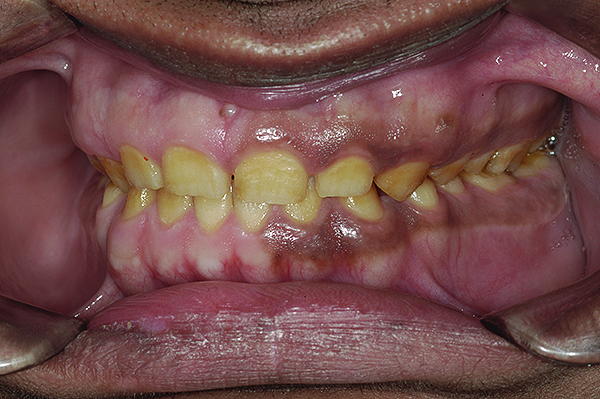

Figure 1. Preoperative frontal smile of patient suffering from AI, showing small, discolored, worn teeth.

Figure 1

The authors report on a 21-year-old patient who presented with severe discoloration and mild sensitivity of teeth (Figure 1). The teeth visible in his smile were very short, unsightly, and unbecoming for his age.

Amelogenesis imperfecta (AI) is an inherited disorder of enamel with mutations in five genes—AMEL, ENAM, MMP20, KLK4, and FAM83H—and a wide range of clinical presentations. It affects the structure and appearance of the enamel of all teeth, both in the primary and secondary dentitions.1 Teeth with this condition tend to be unusually small, discolored, pitted or grooved, and prone to rapid wear and breakage. With generalized compromise of enamel, there is loss of vertical dimension as well as lack of interproximal contacts, resulting in food lodgment and problems associated with it. In most cases the esthetic disability is striking.